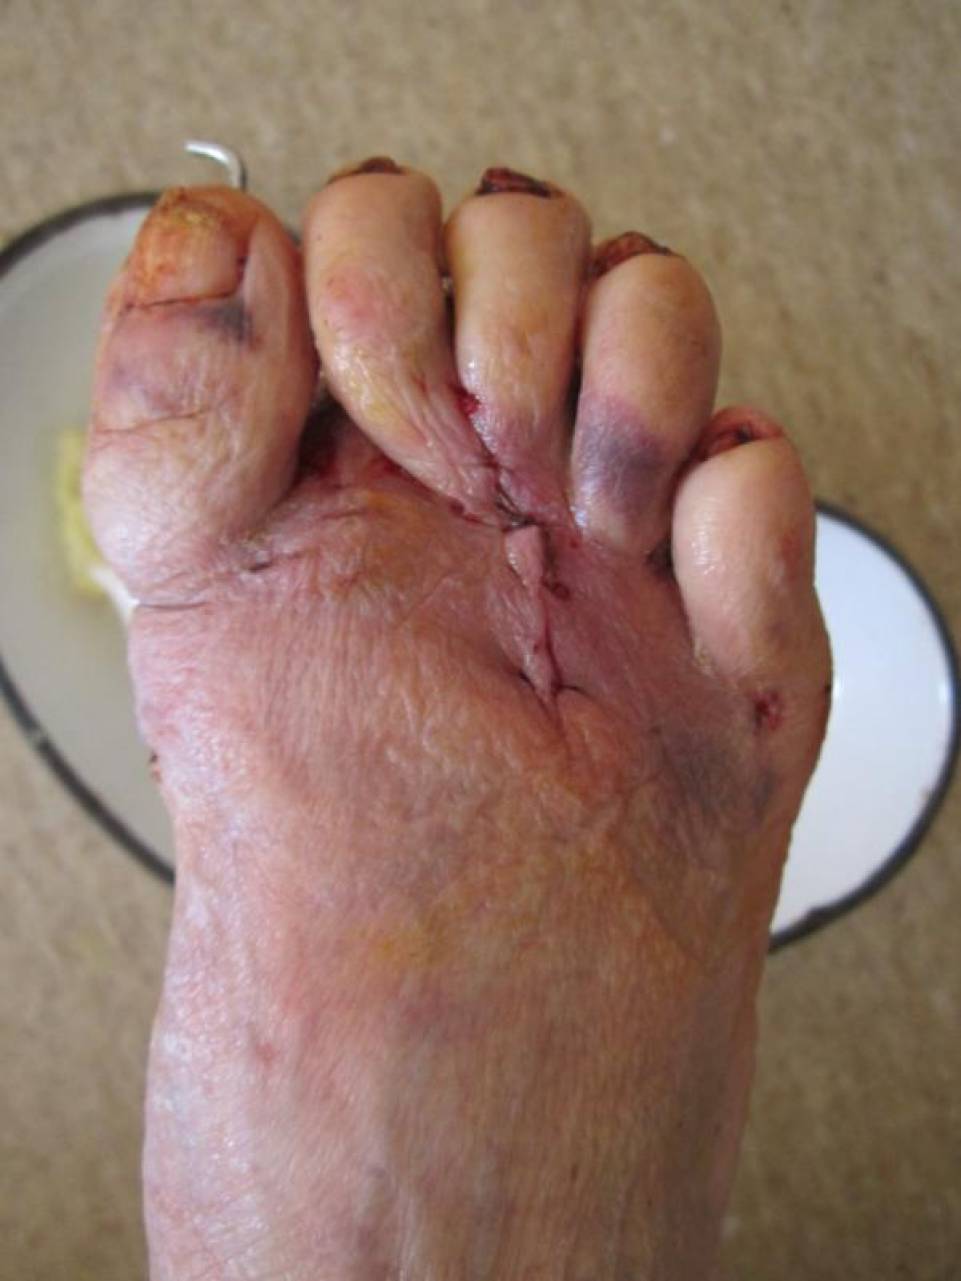

Хорошо бы увидеть фото стопы.

Выкладываю фото стоп в разных ракурсах.

Cдается мне- "болезненный пролежень"- под головкой 2-й плюсневой (выложите фото подошвенной поверхности). Исходя из этого- чрескожные остеотомии 2,3,4 плюсневых плюс-минус фаланг дадут желамеое облегчение пациентке.

Пациентке выполнен артродез 1-ого плюснефалангового сустава, резекции говок 2-3 плюсневых костей, субкапитальная остеотомия 4 плюсневой кости, тенотомиии разгибаталей 2-5 п. стопы. Раны зажили первичным натяжением.